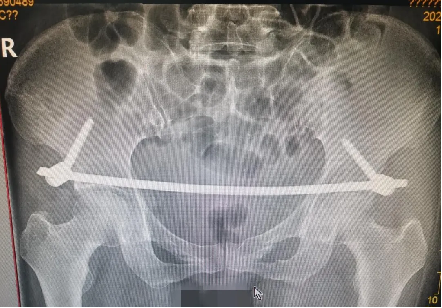

患者黃(huáng)某,因車禍外傷導致全身多處疼痛入院(yuàn),入院即因失血性休(xiū)克於ICU監(jiān)護,完善檢查顯示雙側恥骨粉碎性骨折、右側髂骨多處骨折、右骶髂關節脫位,提示骨盆前-後環均不穩定(dìng)。

對於此種前後環均嚴重失穩(wěn)的複雜(zá)骨盆(pén)骨折的治療,保守治療不僅需長期臥床,易導致褥(rù)瘡、肺部感染、泌尿(niào)係(xì)感染及深靜脈血栓風險,同時勢必影響後(hòu)期功(gōng)能恢複,嚴重降低患者未來生活質量。傳統開放術式手術切口大、手(shǒu)術時間長,手術難度極大,同時存在盆腔內血管神經及膀胱的醫源性損傷風險,以往,遇到此種嚴重(chóng)病情隻能依賴上級醫院專家來(lái)院手術指導,但基於(yú)近期成功開展的骨盆微創治療的經驗支持,外一科董(dǒng)明主任反複(fù)研究患者病情及影像,充(chōng)分(fèn)考慮手術創傷與(yǔ)風險後,決定開展(zhǎn)骨盆骨折(shé)有限切開複位(wèi)內固定術。

經充分術(shù)前準備,由董明主(zhǔ)任、餘策略主(zhǔ)治醫師、葉強醫(yī)師為患者在全麻下僅用不到2小時便成功完成了手術,術中(zhōng)出血量少,術後第二天患者(zhě)就可以床(chuáng)上坐起及翻身,功能恢複良好。